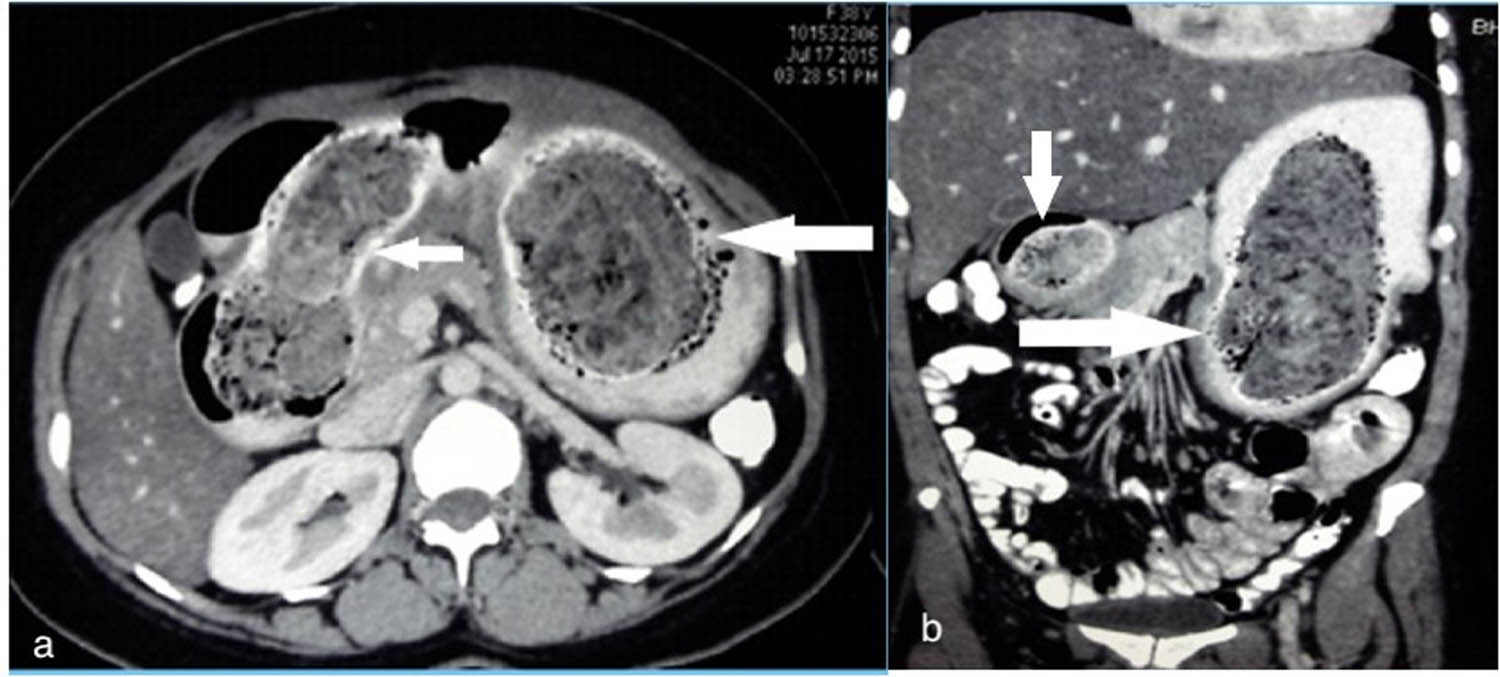

The contrast-enhanced computed tomography (CECT) scan revealed an intraluminal mottled mass of mesh-like appearance occupying the entire stomach and extending beyond the second part of the duodenum, delineated by the oral contrast circumferentially, suggestive of a trichobezoar (Figure 1). The lack of any findings of biliary dilation or the presence of gallstones on the ultrasound further narrowed down the diagnosis.

Axial (a) and coronal (b) CT scan image showing a non-homogenous non-enhancing mass with a mottled appearance within the lumen of the stomach (large arrow) first and second part of duodenum (small arrow).

Ultrasound may show an echogenic mass, but a CT scan is the diagnostic tool of choice since it provides a clear image of the bezoar delineated by the contrast dye, as seen in our case (Figure 1) [13]. Endoscopy also shows a large concretion of hair which is putrid and foul-smelling due to decomposition and fermentation of fats.